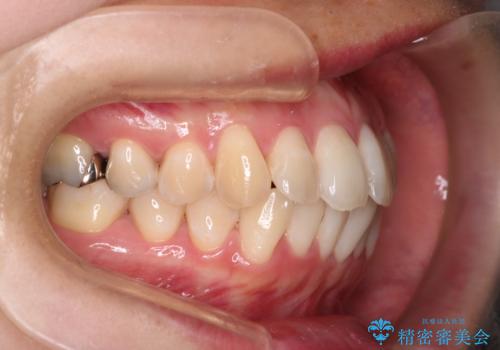

- 前歯のガタガタを主訴に来院された患者様です。

前歯の傾きも少し内側に入るように計画をたて、インビザラインにて治療を行いました。

このぐらいのガタガタであれば、インビザラインで簡単に治すことができます。